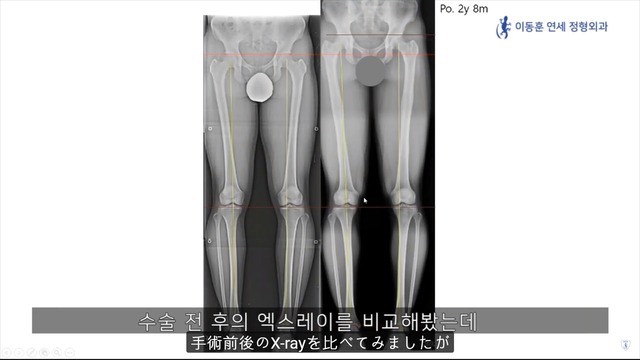

身長手術後の運動能力回復がどうなるか Dr. Donghoonのブログ

手術で太もも5cm伸ばした

スクワット110kgが一応できる

こんな感じらしい